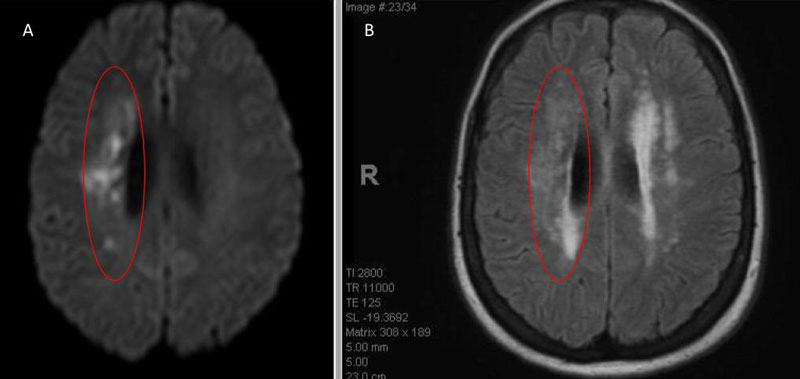

An MRI confirmed diffusion and FLAIR positive ischemic strokes within the deep periventricular white matter compatible with a “watershed” distribution of injury (Figure 3).

Figure 3. A) MRI Diffusion and B) FLAIR sequence confirm ischemic damage in the right periventricular deep white matter “Watershed” territories.